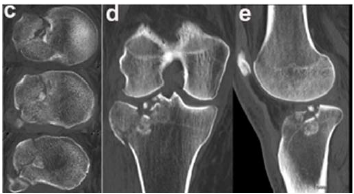

Um paciente de 39 anos de idade, vítima de queda de bicicleta, sofreu trauma no joelho direito. Foi levado ao pronto-socorro do hospital mais próximo, onde foram realizadas as radiografias apresentadas.

O quadro clínico desse paciente se caracteriza por dor

Enunciado 4335213-1

O exame de imagem mais apropriado para o estudo do caso é

Enunciado 4335212-1

Geralmente, o mecanismo de trauma dessas fraturas envolve